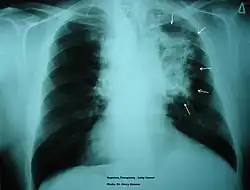

Cancer

Tobacco smoking has been associated with cancer mainly along the respiratory tract, but may also lead to cancer in the bladder and renal pelvis.[24] Upon smoking, carcinogenic chemicals are inhaled, affecting the inflammation response. As inflammation plays an important role in inducing cancer, with smoking affecting the inflammatory response of macrophages in the lungs, the dysregulated inflammatory response poses a higher risk in developing cancer along the airway. Symptoms of cancer mediated by cancer include lumps on the body, sudden weight loss, persistent coughing and tough swallowing. Treatments for cancer are generally surgery, chemotherapy and radiation therapy. These treatments directly target the cancer cells to kill the cancer prior to smoking rehabilitation programs.